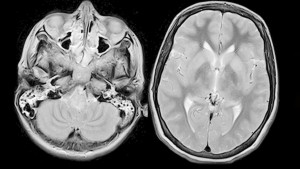

4. Üçüncül Evre: Eğer tedavi edilmezse, sifiliz üçüncül evreye ilerleyebilir. Bu evrede iç organlar, cilt ve kemikler ciddi şekilde etkilenebilir. Bu evre özellikle kalp, beyin ve sinir sistemine zarar verebilir.